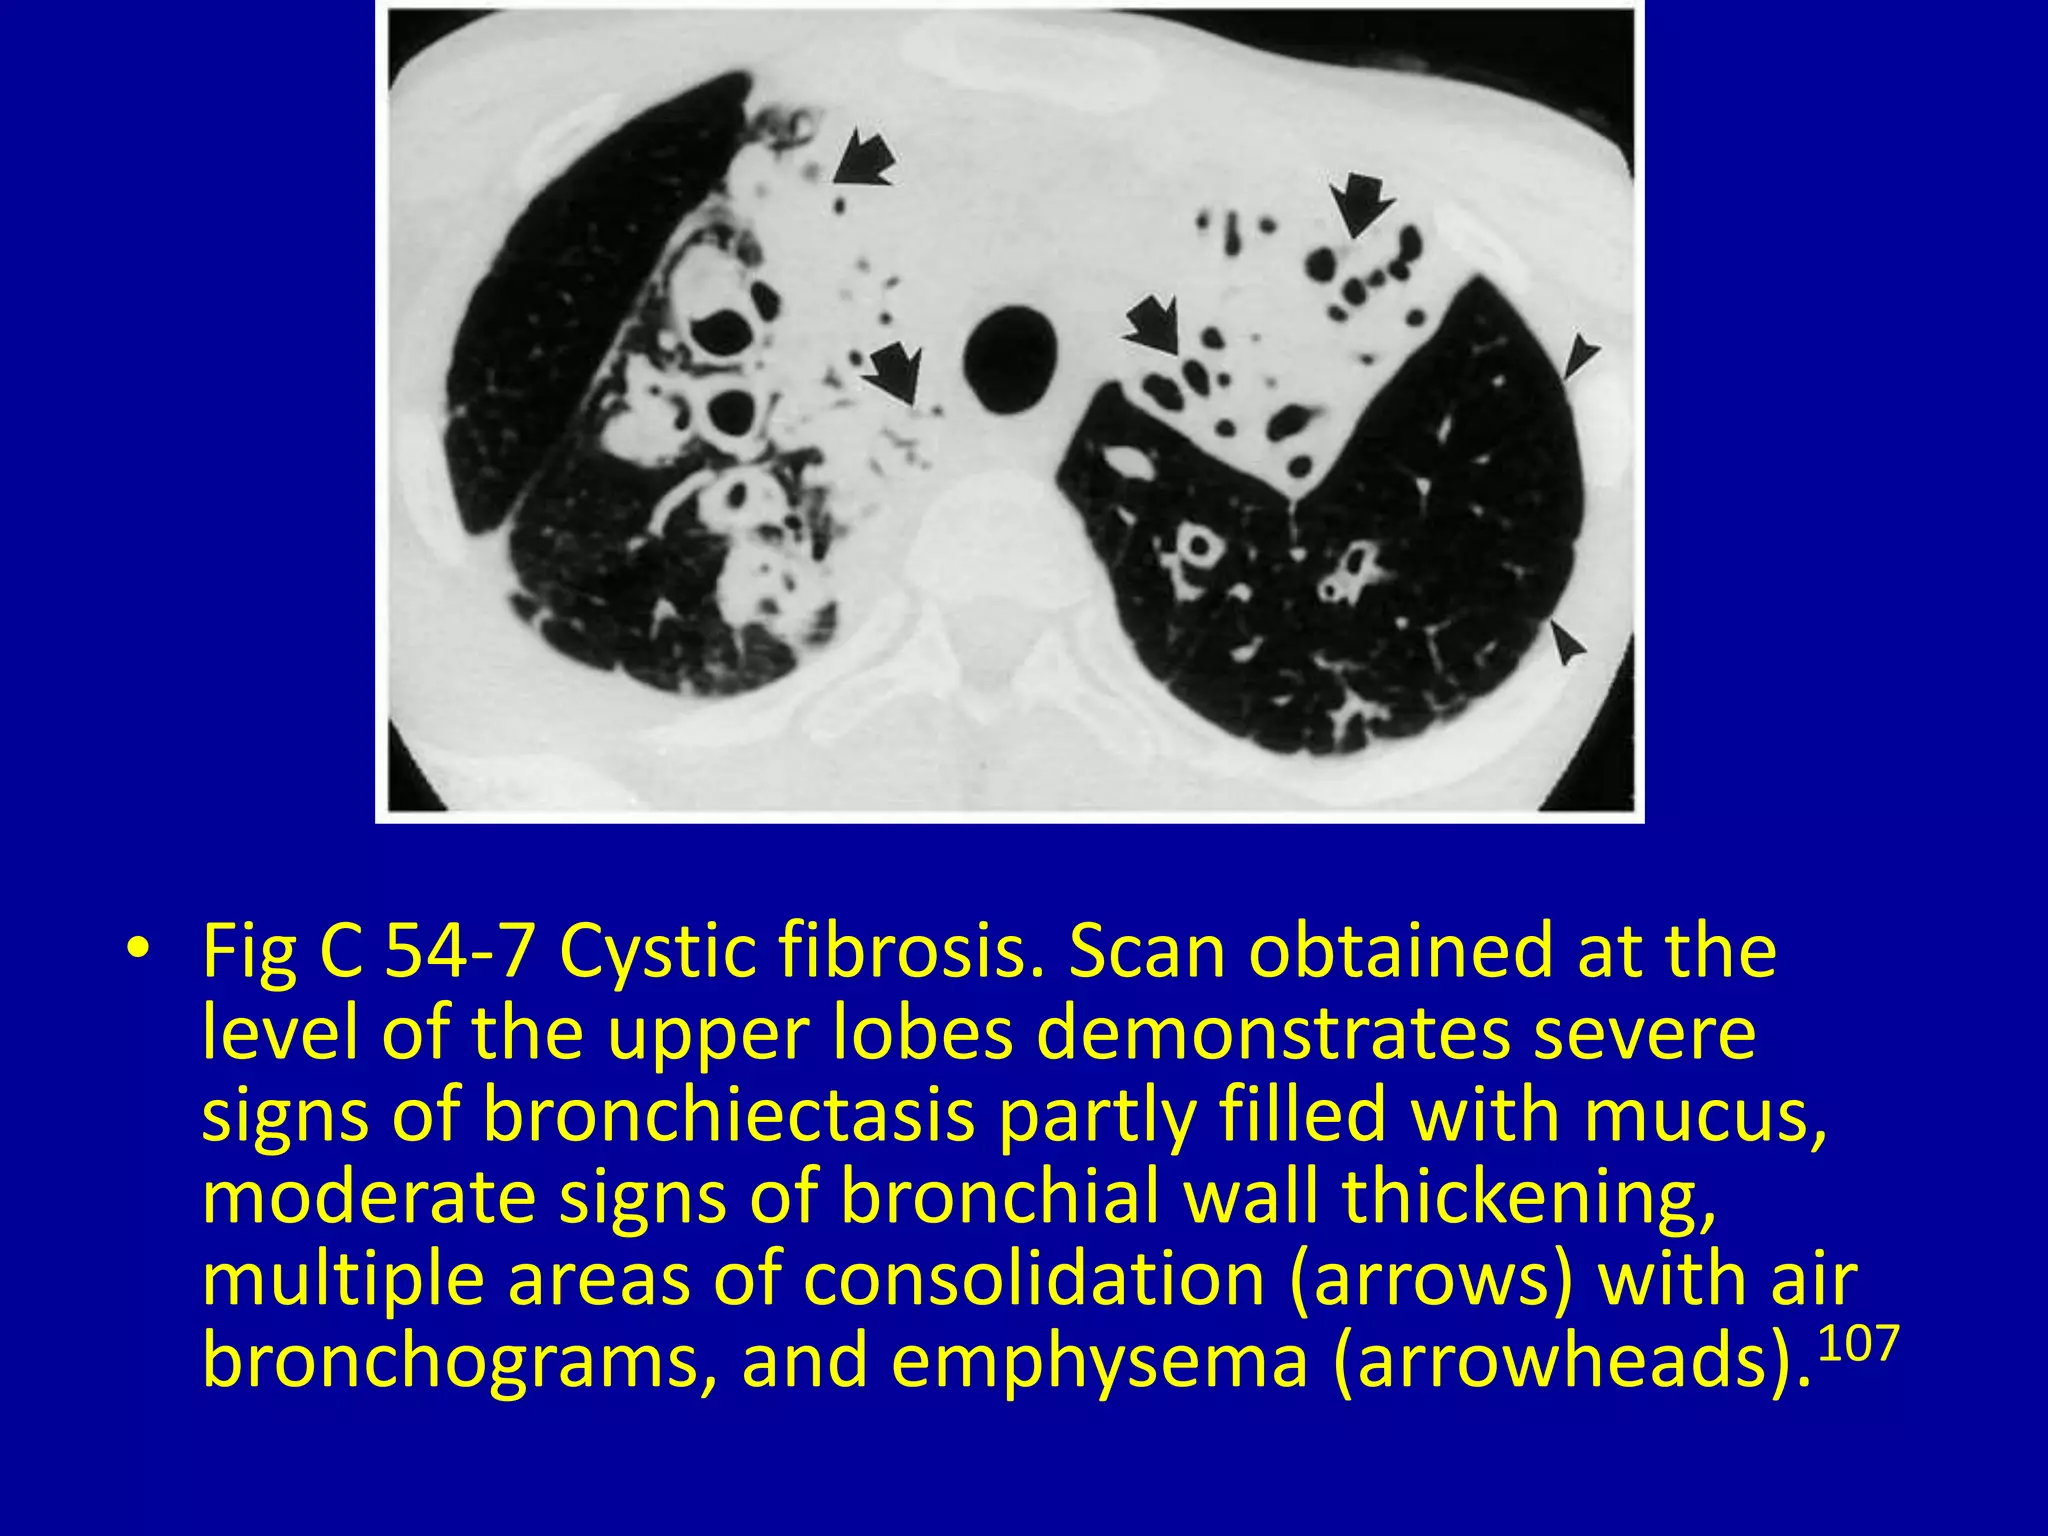

This document discusses various pulmonary diseases that predominantly affect the upper zones of the lungs. It includes 10 figures showing CT scan findings of different conditions like postprimary tuberculosis, sarcoidosis, pulmonary Langerhans cell histiocytosis, silicosis, centrilobular emphysema, chronic eosinophilic pneumonia, cystic fibrosis, allergic bronchopulmonary aspergillosis, neurogenic pulmonary edema, and ankylosing spondylitis. The images demonstrate lesions, nodules, consolidations, cysts, and other abnormalities that are largely limited to the upper lobes and regions of the lungs.